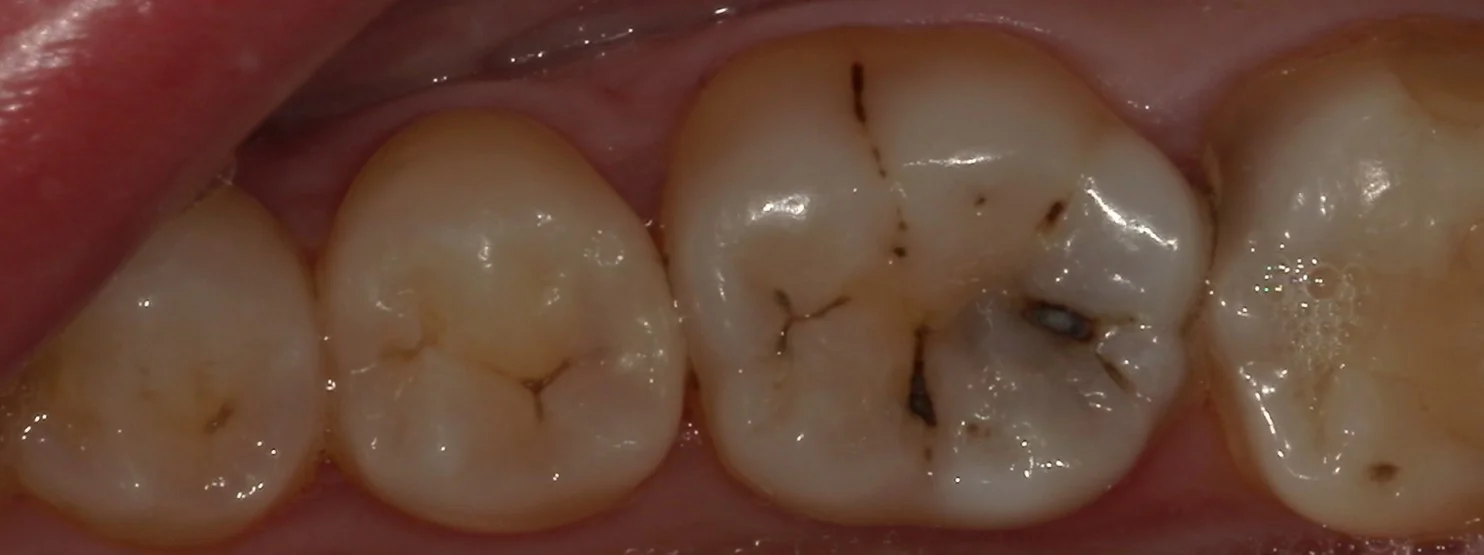

さて、では術前から。

どこが虫歯が変わりますかね?

1か所はあからさまに黒いのが透けているので分かりやすいかもしれませんね。

軽く削って、虫歯が見えやすくなった状態がこちら。

どうです?

結構黒いのが分かりやすくなりましたよね?

また、手前の歯との間にも黒い部分があるのが分かるかと思います。

削っているので分かると思いますがもちろんここも虫歯です。

上の術前の写真では非常に分かりづらく、拡大鏡で覗いても油断すると見逃してしまいそうな状況でした。